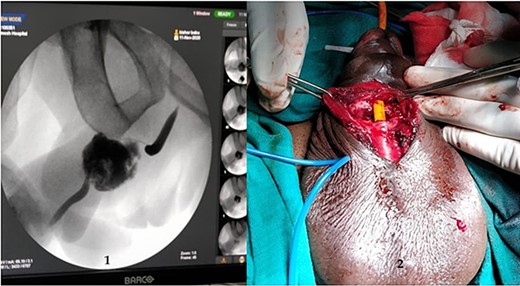

A 37-year-old male presented with a history of a ‘snap’ sound and immediate detumescence of penis during intercourse, when he fell and hit the pubic bone of his partner. There was generalized swelling and pain in the penis. There was acute retention of urine, an attempt to pass a catheter failed and the patient underwent supra-pubic catheterization. On examination, there was classical ‘eggplant deformity’ of the penis with blood at the tip of the meatus. MRI showed a tunical tear on both sides at the penoscrotal junction with indistinct urethra and extensive hematoma in the proximal penile shaft (Fig. 1). With the diagnosis of a fractured penis and possible urethral injury, after proper counselling, the patient was taken up for surgery. On the table, a retrograde urethrogram (RGU) was done showing evidence of partial urethral disruption. On exploration with penoscrotal vertical incision, there was total transection of proximal penile urethra, and a 1.5 cm tunical injury of corpus cavernosum on both sides ventrally (Fig. 2). There was extensive hematoma. Corpora sutured with 4.0 prolene after reconstructing the midline septum. Urethral ends mobilized and anastomosed with 3.0 vicryl in a single layer with minimal spatulation (Fig. 3). The patient was discharged on the 5th post-operative day; Foley catheter was removed on day 21. Follow-up RGU done after 3 months showed no evidence of stricture (Fig. 4).

An MRI with (1) left corporeal tear on the left side with surrounding hematoma and (2) right corporeal tear with hematoma and disruption of urethra.